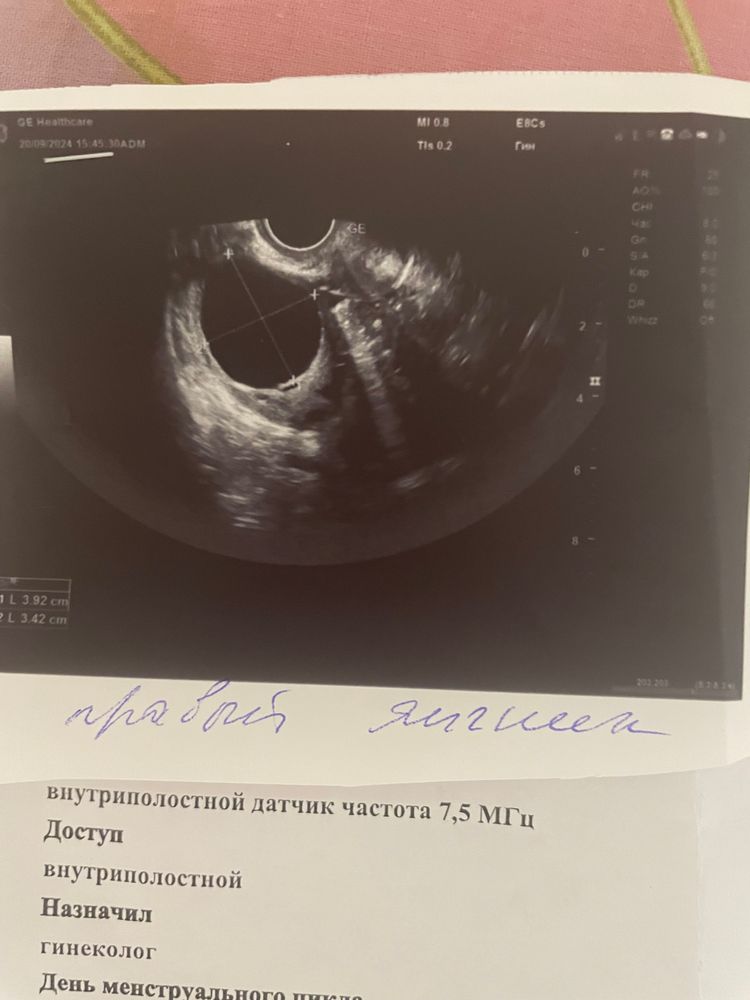

На фото фолликулярная киста 3.92 см*3.42см. однокамерное округлое новообразование.Внутренняя поверхность гладкая.стенка тонкая, содержимое однородное. черное на узи - это жидкость. На жт или кисту жт не похоже

У кисты жёлтого тела неровные и более плотные края...у вас тонкие края и ровные, это фолликулярная киста...ничего страшного, пройдет сама за 1-2 цикла, у меня много раз была иифоликулярная и киста ЖТ, даже размером 6 см, проходила сама без лечения, как миленькая...считаю все эти лечения пустая трата нервов и денег...это как,если лечить простуду, то она пройдет за 7 дней, а если не лечить, то за неделю)..организм сам умеет и знает как такие функциональные кисты убирать... главное тяжести не носите, резких движений не делайте, и па аккуратнее...